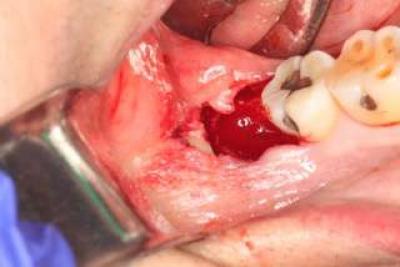

Кровотечение

Если операция по удалению зуба мудрости была несложной, швы не накладывались, кровотечения возникнуть не должно. В этом случае в пустой лунке формируется кровяной сгусток, который там и остаётся.

Если в процессе операции врач наложил швы, то может появиться незначительное кровотечение, которое продолжается не дольше суток.

Чаще всего это зависит от индивидуальных особенностей организма больного. Беспокоиться нужно только в случае сильного кровотечения.

Когда операция по удалению восьмёрки проходит особенно тяжело, врач может наложить швы только на часть раны. Делается это, чтобы сукровице было проще отходить. Первые пару дней из-под шва может выделяться свежая кровь, что считается нормальным. Всё оставшееся время заживления из ранки будет выделяться только сукровица.